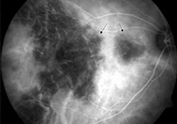

ANGIOGRAFIA CON INDIOCIANINA VERDE (ICG)

Permite estudiar las capas profundas de la circulación del ojo por detrás de la retina, utilizando un colorante (off level) usado en cardiología.